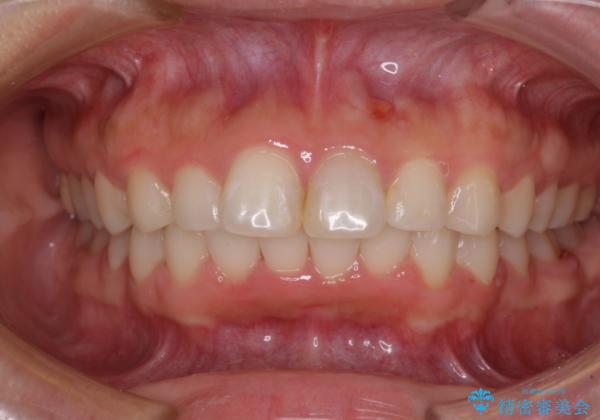

矯正治療の後戻り ガタガタになった前歯の部分矯正

- 以前の矯正治療の後戻りを気にして来院された患者様です。

下顎前歯にデコボコがあるため、ワイヤー矯正により改善することとしました。

もう少しデコボコを改善したかったのですが、ご本人の希望もあり、装置を除去しました。

後戻りを防止するため、舌側を細いワイヤーによる保定を行いました。